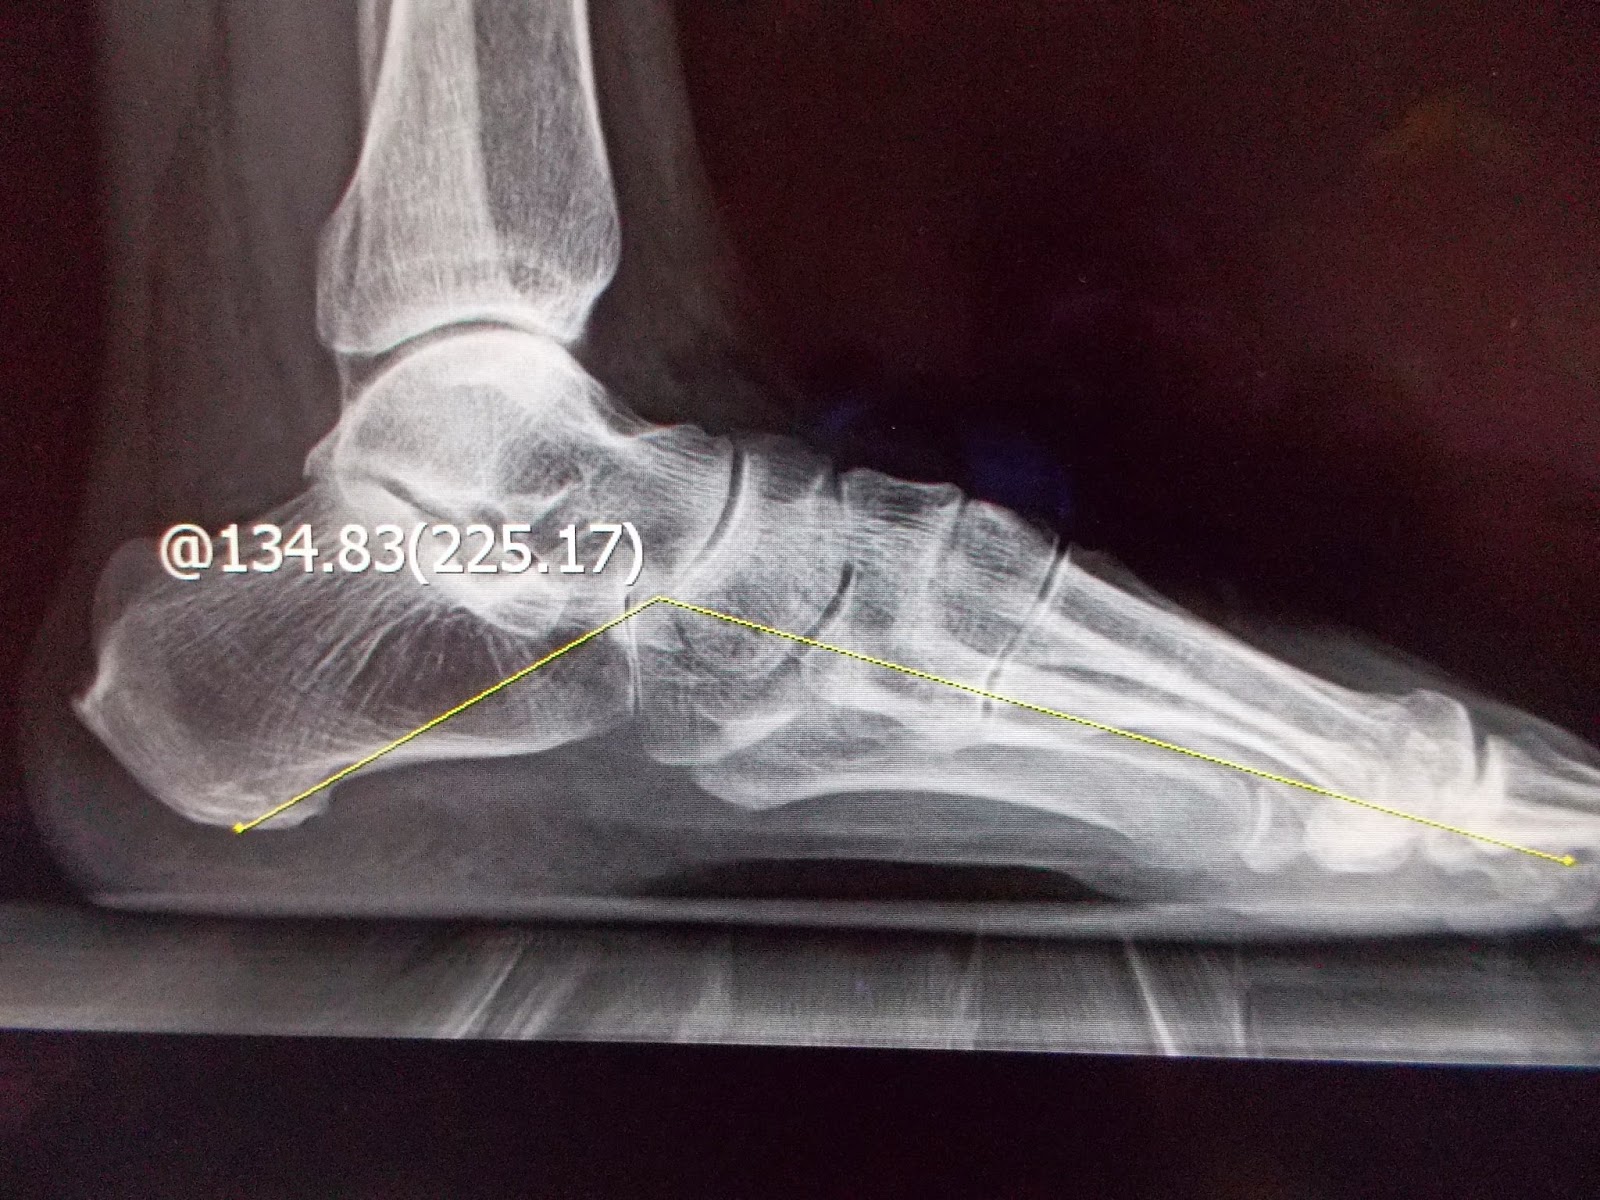

赤腳走路更可看出其特有的內傾(pronation)步態;以特定角度照的X光,更可看到某些負重骨骼間的相關角度有差異,或關節骨頭的一些變化(如圖),診斷並不困難。

(左圖:扁平足並足底筋膜炎. 右圖:扁平足 因距-舟狀骨關節退化及跗底肌腱炎 腳痛)